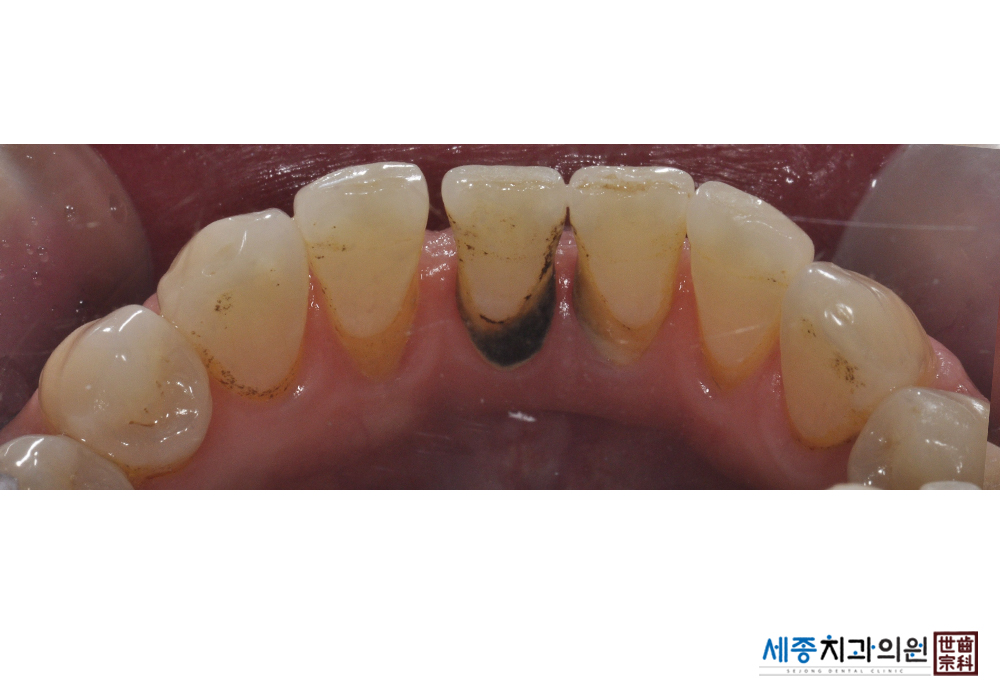

[스케일링] 치주질환 예방 스케일링 치료

치료전 : 2019-01-19

가글마취&저주파 스켈러를 사용한 스케일링